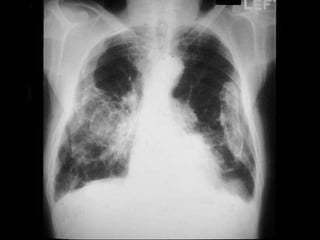

Pathologic features

• Begin in lower lobes and sub pleura

• Early stages – minimal fibrosis

• Late stages- extensive fibrosis- destroys the

architecture-dilated/cystic air spaces-

honeycombed appeareance

Pathologic features • Beginin lower lobes and sub pleura • Early stages – minimal fibrosis • Late stages- extensive fibrosis- destroys the architecture-dilated/cystic air spaces- honeycombed appeareance